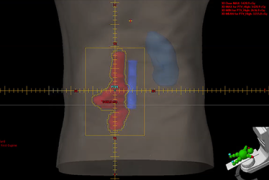

IMRT – Radioterapia de Intensidade Modulada e VMAT – Arcoterapia Volumétrica Modulada